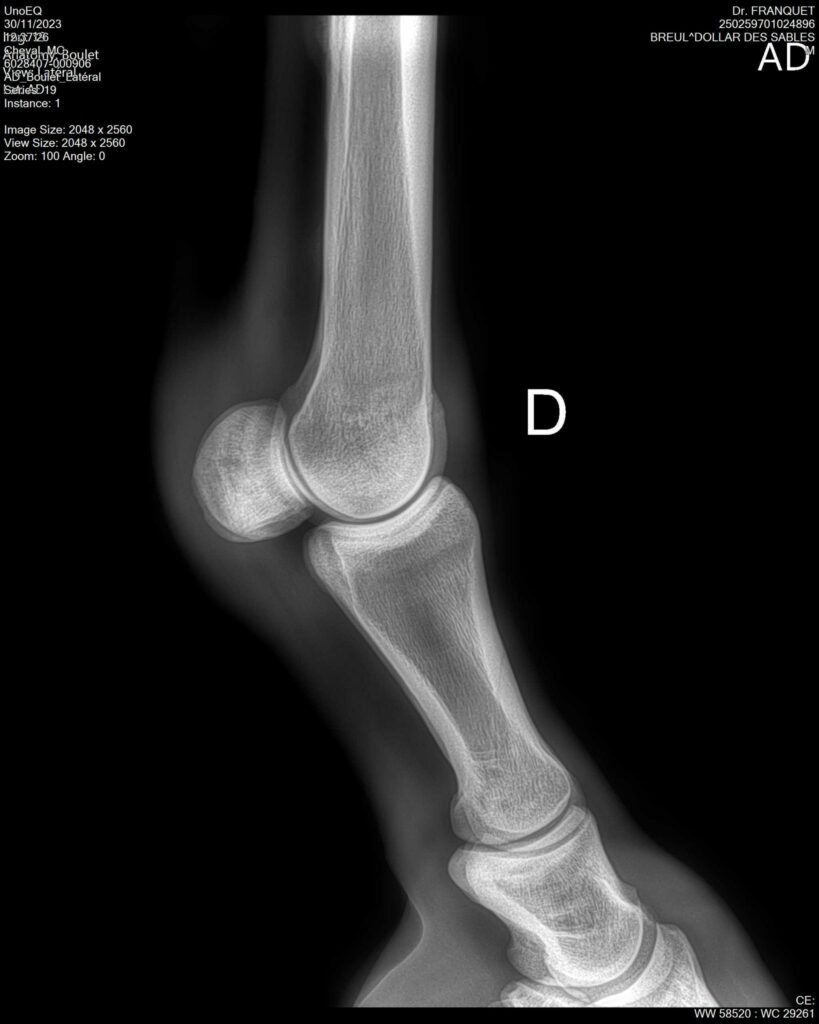

DOLLAR DES SABLES, Selle Français, hongre, 12 ans par DOLLAR DE MURIER x ABKE (ACORADO). Classé 135 avec professionnel à fait 125 avec amateur, récemment classé sur amateur 1GP 120. Très beau modèle ! Gentil cheval, respectueux avec des moyens et du sang. Transport OK, maréchalerie OK, santé RAS, Bilan clichés radios OK.

RADIOS